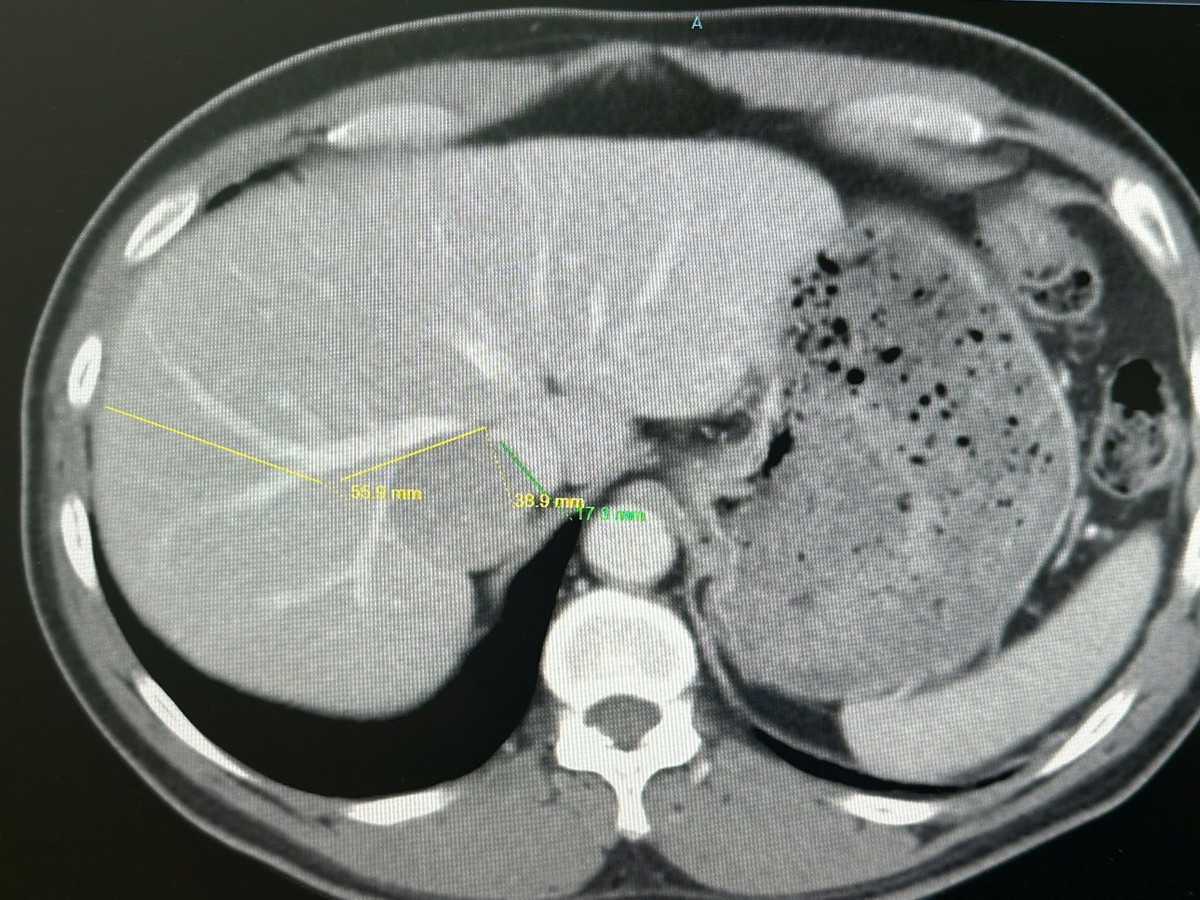

Khối u gan kích thước lớn nằm ở vị trí phức tạp - Ảnh BVCC

Một năm sau, khi tái khám, siêu âm ghi nhận khối bất thường tại gan. Kết quả chụp cộng hưởng từ (MRI) cho thấy khối u gan kích thước khoảng 4 cm. Do khối u nằm ở vị trí hiểm hóc, bệnh nhân được cả hai bệnh viện tư vấn nên điều trị bằng các phương pháp khác thay vì phẫu thuật vì rủi ro quá lớn.

Sau đó, bệnh nhân được chuyển đến Bệnh viện Quân y 175 để tiếp tục thăm khám và điều trị. Qua các xét nghiệm và chẩn đoán hình ảnh chuyên sâu, các bác sĩ xác định khối u kích thước khoảng 4 cm nằm sát vây quanh bởi nhiều mạch máu quan trọng, đặc biệt là tĩnh mạch gan phải và tĩnh mạch chủ dưới.

Vị trí này khiến việc tiếp cận và cắt bỏ khối u trở nên rất khó khăn, bởi chỉ cần một sai sót nhỏ cũng có thể gây tổn thương mạch máu dẫn tới chảy máu lớn, nguy hiểm tới tính mạng người bệnh.